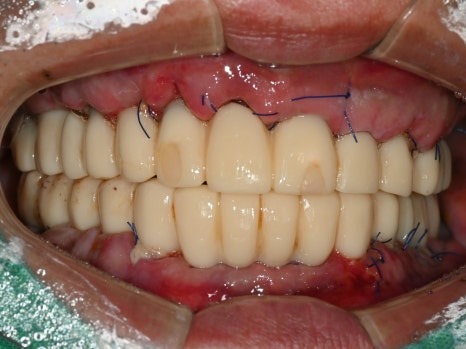

수술 당일

수술 2일 후

수면마취로 17개의 임플란트를 식립하였고,

월요일에 임플란트 즉시 기능 치아(임시치아)를 끼워드렸습니다.

치료 전

수술 2일후

몇 개월이고 기약 없이 임시 틀니를 써야한다는 걱정에

치료를 시작하지 못하셨던 환자분은

수술 2일 만에 고정된 치아가 완성되자

놀라워하시면서 식사가 가능하게 된 걸

너무 좋아하셨습니다.